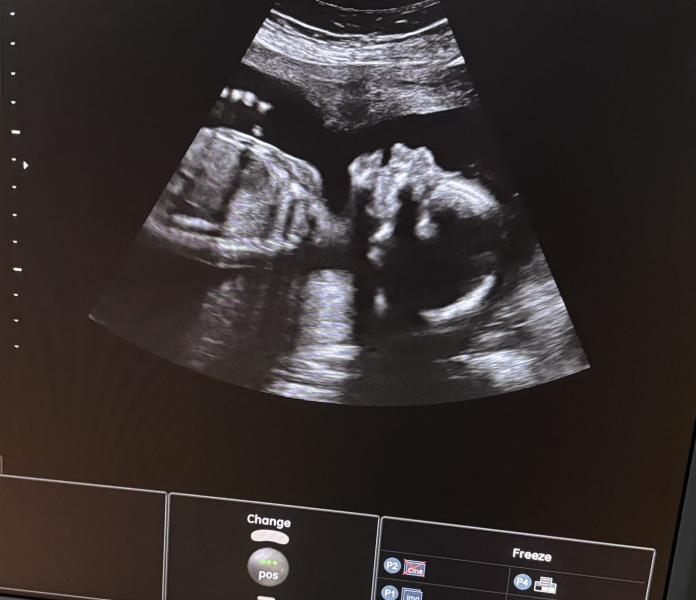

Второй скрининг пройден 👍 с ребеночком все хорошо, писюн не отрос 😁 мы ждем тебя💜

Да думаю вряд ли разные врачи могут ошибиться 😁

Тем более я делала в генетическом центре, где делают скрининг у кого были или есть проблемы